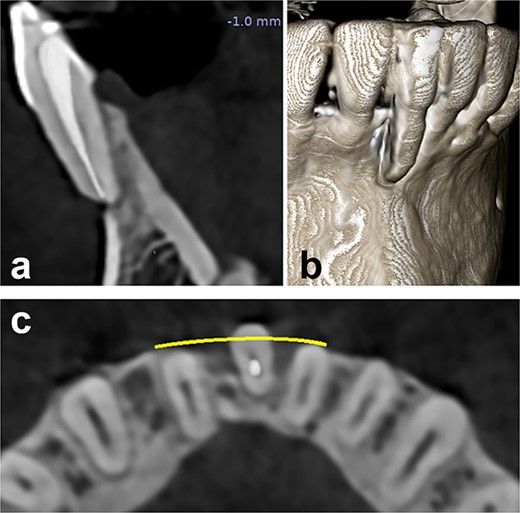

A radiographic examination of the anterior mandibular region revealed no interdental bone loss. However, the affected tooth had previously undergone root canal treatment due to hypersensitivity. CBCT analysis revealed a root protrusion of the affected tooth (Fig. 2a–c).

Preoperative radiographical status, (a) sagittal section, (b) 3D construction view, and (c) axial section.